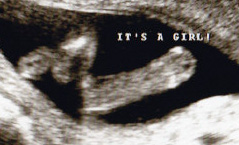

Woooohoooo!!! IT'S a GIRL!!!!! :cheerteam: :DD: CONGRATULATIONS!!!!!

ALL girl, Congrats, so happy for you xxx

That is soooo all girl!!! I am thrilled for you, happy heart!! Yay!!! I just had a gut feeling about you!